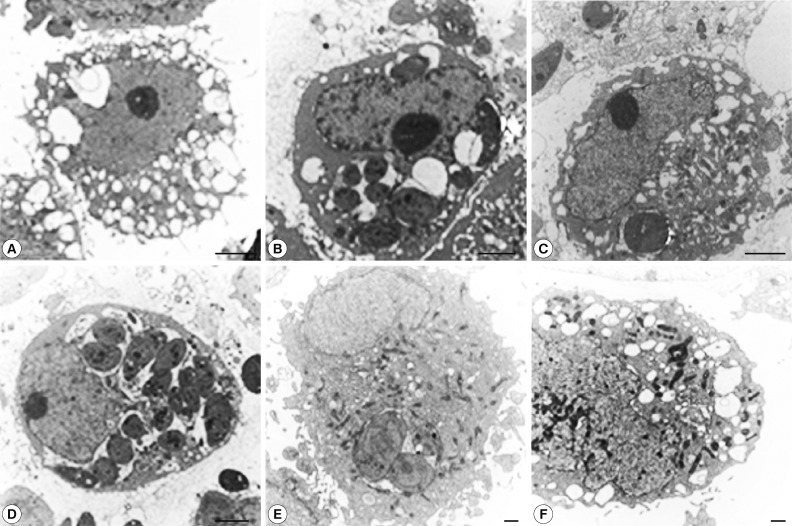

The formation of autophagic vacuoles is thought to be induced by Beclin 1 (Atg6), one of the proteins required for the autophagic process [11,12]. It has been found to promote cell survival and it may function as a tumor suppressor in specific conditions [13]. Autophagic vacuoles were detected by monodansyl cadaverine (MDC) staining and transmission electron microscopy (TEM). In this experiment, we found that cell autophagy is inhibited by T. gondii proliferation.

MDC staining

HeLa cells (1×106) were cultured in 12-well culture plates on cover glasses for 6 hr at 37℃, 5% CO2 in RPMI 1640 with 10% FBS. The cells were infected with T. gondii (cell: tachyzoite ratio=1:5) and/or rapamycin and incubated for 6, 18, and 24 hr. A stock solution of 10 mM MDC, the autofluorescent dye, was prepared in DMSO and the cells were incubated with 0.05 mM MDC at 37℃, 5% CO2 for 1 hr. After washing a fixation-permeabilization solution (Becton Dickinson, San Jose, California, USA) was added for 15 min [16]. After fixing, the cells were washed 3 times with a permeabilization-washing buffer, transferred to glass-slides and observed under a fluorescence microscope (DMRE, Leica, Germany).